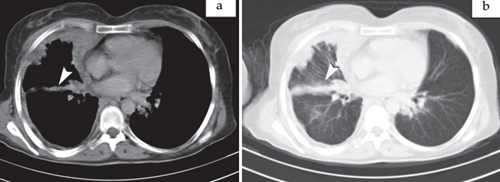

Mesothelioma images > Fig. 1. Axial contrast enhanced CT parenchymal (a.) and mediastinal sections (b.) shows

nodular, irregular and circumferantial right sided pleural thickening in 55 year-old man. Note that contracted right hemithorax and anterior mediastinal lymph node (arrow head). We can see pleural calcification on left sided pleural surface (arrow head).